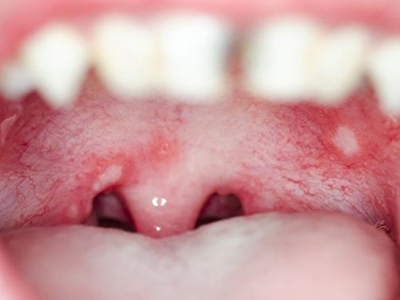

口腔溃疡又称复发性口疮,是慢性的口腔黏膜小溃疡,深浅不等,为圆形或椭圆形损害,可反复和周期性复发。多发生于口腔非角化区,如唇黏膜、舌头等处,预后较好,可自行痊愈。

口腔溃疡为圆形或椭圆形,直径0.2-0.5cm,溃疡单个或由数个连成一片,溃疡表浅边缘整齐,外观呈灰黄色或灰白色,上覆盖黄白渗出膜,周围黏膜充血、水肿而有红晕。

皮损局部有烧灼样疼痛,于进餐时加重,影响进食、说话。严重溃疡直径可达1-3cm,深及黏膜下层甚至肌肉。